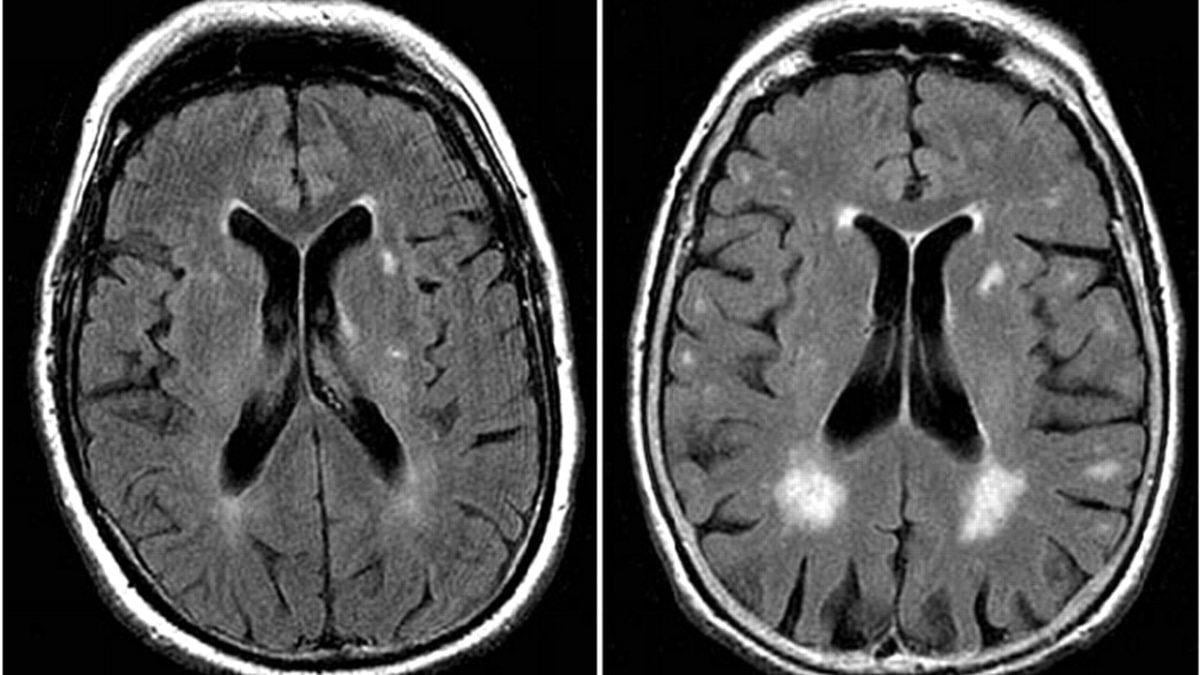

結果發現,患有代謝問題的肥胖人士,磁力共振檢查顯示腦部損傷較多,出現失智情況也較為普遍,反映代謝問題不但影響體重,也可能對大腦造成傷害。有關已於《Diabetes, Obesity and Metabolism》發表。

患有代謝問題的肥胖人士,磁力共振檢查顯示腦部損傷較多。